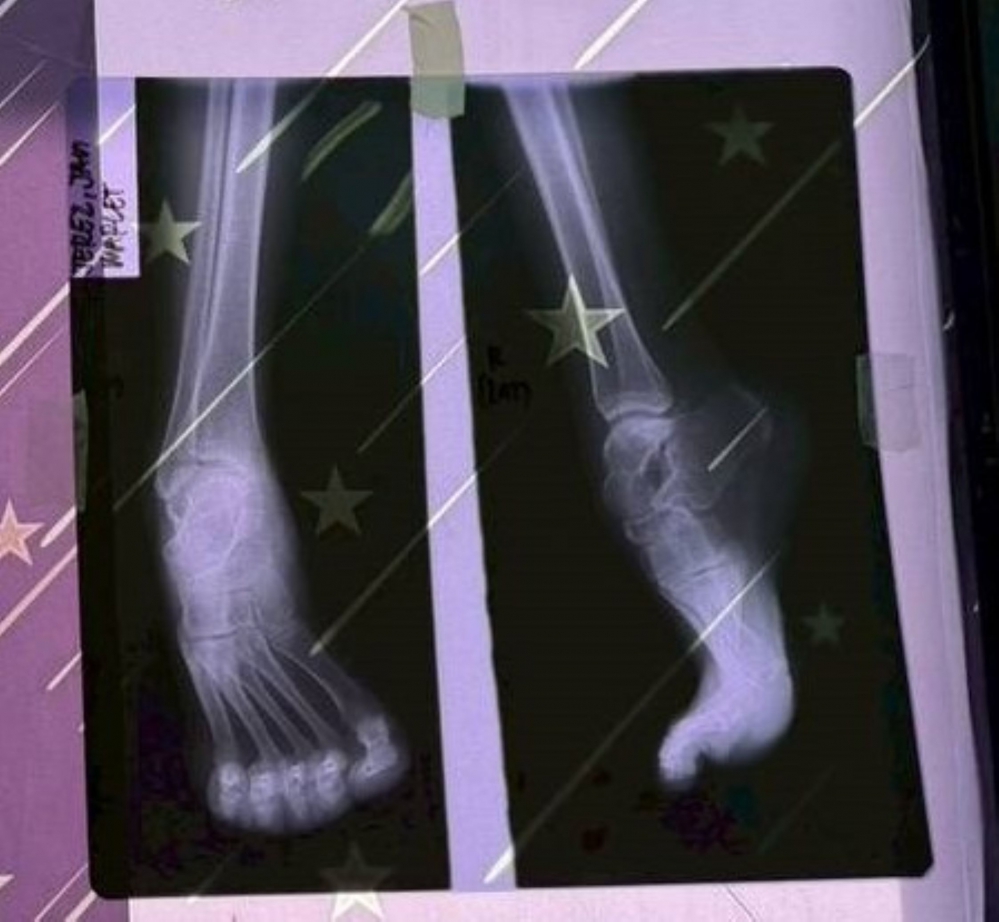

此次義診行動中,一名患有足部畸形的少女格外牽動醫療團隊的心。嘉基團隊在2025年短宣行動時首次見到她,因先天足部結構異常,她長期行走困難,也因外觀差異而缺乏自信,生活與求學都受到影響。醫療團隊返台後即開始規劃後續醫療協助,並在此次行動中攜帶更完整的設備與專業人力,為她進行足部矯正手術。

手術順利完成後,少女的足部外觀明顯改善,也有助於提升未來行走與日常生活能力。醫療團隊表示,希望透過這次手術,為她的人生帶來新的契機。隨著術後逐步恢復,她也將有機會重新回到校園,展開新的學習與生活。